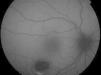

Ophthalmic examination showed the anterior segment to be normal in both eyes. The right eye presented an oval-shaped hypopigmented lesion in the lower temporal sector of the macula, pointing to the fovea, and measuring 1.7mm vertically and 2.3mm horizontally (Fig. 1).